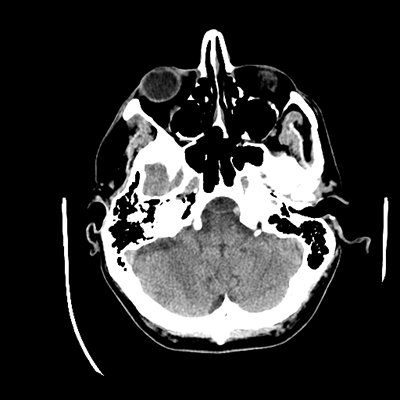

A 51 year-old man with metastatic RCC (diagnosed in 2010, previously on ipilimumab/nivolumab, now on cabozantinib since 2022) with known multifocal brain metastases c/b symptomatic focal epilepsy (on levetiracetam) initially presents to the ED due to subacute progressive gait difficulties. He's been experiencing some unsteadiness and weakness of his left leg. He does require use of a cane, but he hasn't had any falls. His last seizure was one year prior; he's had none since his levetiracetam was increased to 1.5g bid.

In the ED, he undergoes a non-contrast head CT. You are then consulted.

NCHCT

Unclear at this point actually. Of course, our initial priority is to maintain the ABCs. He's somnolent now, but his mentation should begin to gradually improve in the next few minutes. Again, the question of cEEG is actually a question of "what are we trying to answer with this test?" His recent history hasn't been concerning for seizures, though we knew he is at high risk for them due to his multiple supratentorial metastases and resultant symptomatic focal epilepsy. We also know now that his metastases have bled, which is concerning and also not unexpected given the malignancy type. The fact that he has epilepsy doesn't mean that you necessarily need to start cEEG after every single seizure.